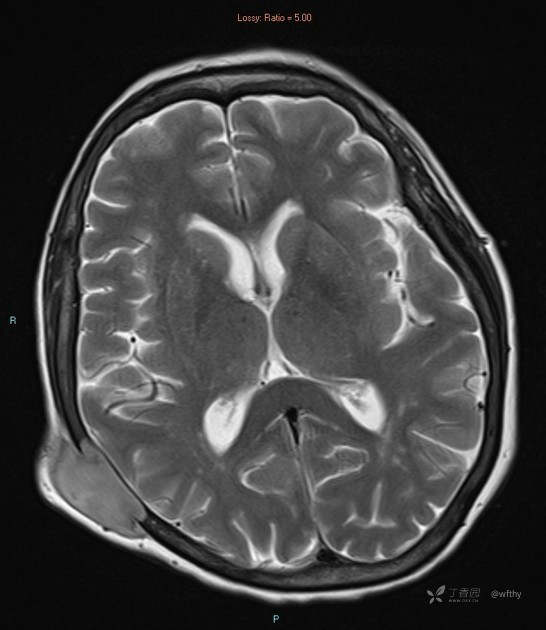

病例女65,头部肿块